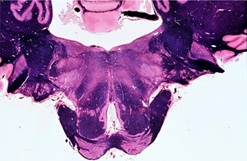

Tracts and Nuclei

Please click one of the following photos to enter the respective section.

Section #2